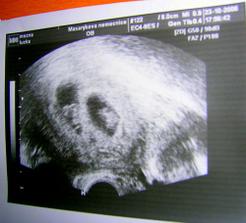

18.září jsme byli na našem 1.IVF... a 8.den od ET se mi "zjevily" nádherné // 🙂... přeju si,aby se všechno vyvíjelo dobře... 29.9 11.den po ET mi pro zhoršení OHSS provedli punkci Douglasova prostoru a odsáli 2 litry žlutého ascitu ☹ Nicméně se mi ulevilo 🙂 HCG ten den 259... 6.10 kontrola HCG - 2950 (18.den od ET)... 10.10 UTZ - čekáme DVOJČÁTKA 🙂 🙂 🙂... 17.10 krvácení a následná hospitalizace, UTZ - dvojčátkům bijí srdíčka, 20.10 HCG - 56000, 25.10 propuštění z nemocnice... 31.10 poslední kontrola v CARu, dvojčátka mají 2 a 2,1 cm... 11.11 UTZ - dvojčátka mají 3 cm... 24.11 UTZ - dvojčátka mají 9 cm (ale moc se mi to měření nezdá, ve čtvrtek na screeningu se ukáže pravda, čeká nás 3D 🙂) 27.11 screening I.trimestru - miminka jsou zdravá, od hlavičky po prdelku mají 7 cm... 19.12 3D - miminko "A" je chlapeček, "béčko" chce zůstat zatím v utajení 🙂 tak snad příště 🙂... 8.1 3D - miminko "B" je holčička 🙂 19.1 echokardiografie - obě srdíčka jsou zdravá 🙂 20.1 screening II.trimestru - vše OK, miminka mají 360 a 364 gramů 🙂 26.1 UTZ - chlapečkovi se ztratil pindík a najednou čekáme 2 holčičky 🙂) Doufám, že už je to definitivní 🙂) 19.2 UTZ 3D4 - holčičky potvrzeny!!! 🙂 mají každá téměř 800 gramů! 🙂 20.3 UTZ - holčičky mají 1700 a 1800 gramů! 8.4 UTZ - holky mají neuvěřitelné váhy 2415 a 2600 gramů! 11.5 nástup do nemocnice... 11.května ve 20,03 se nám akutním císařským řezem narodila Eliška (2970/48) a o minutu později Nelinka (3200/50).Jsme nejšťastnější rodiče na světě! 🙂